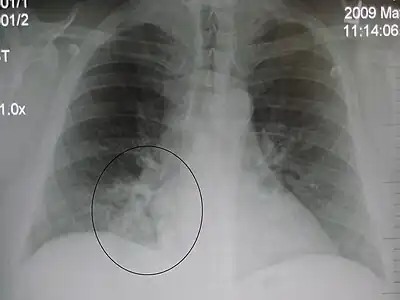

AP CXR showing right lower lobe pneumonia

Right upper lobe pneumonia as marked by the circle.